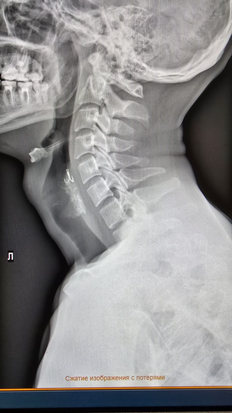

О необычном случае на рыбалке рассказали в пресс-службе Красноярской краевой клинической больницы. В медучреждение поступил пациент, в пищеводе которого застрял инородный предмет. Оказалось, что перед тем, как попасть в больницу, гражданин ловил рыбу. Однако рыбалка закончилась для него не поездкой домой с хорошим уловом, а госпитализацией.

– Рыбак держал крючок во рту, стоя в лодке. В какой-то момент из-за сильного ветра лодка качнулась, толчок и он рефлекторно сделал глотательное движение. Так крючок оказался в пищеводе, – сообщили в пресс-службе.

Медики пришли на помощь рыбаку и с помощью аппарата ФГС и щипцов избавили его от опасного предмета. Возраст пациента и другие подробности не разглашаются. Об этом пишет издание Newslab.ru.